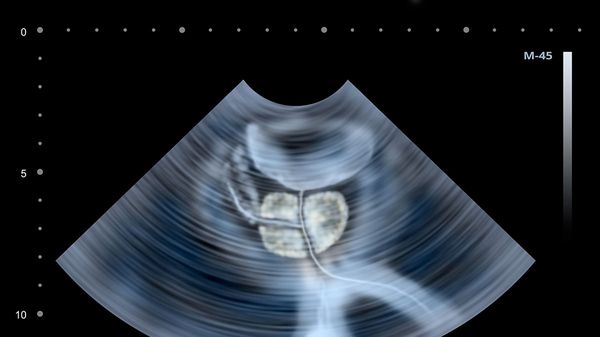

IL SUMMIT INTERNAZIONALE. Bergamo ha ospitato la 13ª edizione della Conferenza internazionale sulle problematiche da trombosi ed emostasi nel cancro.